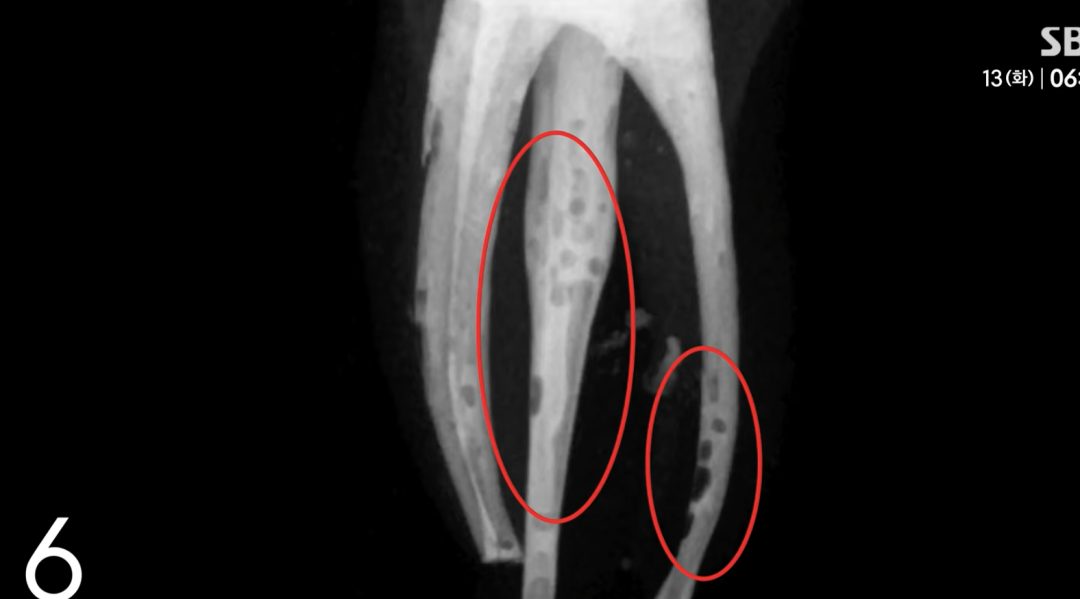

原始照片的显示,由于填充物不足,患者的牙根部位留有缝隙和气泡,这些是治疗不完善的表现。

而学生提交给学院的照片却经过精心处理,所有问题都被PS给“修复”了,营造了完美填充、治疗成功的假象。

(x光片照片ps前后对比)

(PS前的牙齿)